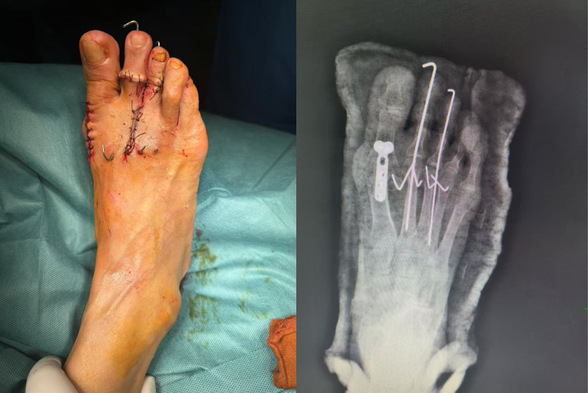

第三代拇外翻微创术后

这三位患者均为足拇趾外翻多年,随着年龄增长,外翻的程度越来越严重,穿鞋困难、疼痛难忍,已严重影响到日常生活,于是来到我院骨外四科就诊。在骨外科主任邢星的带领下,经过术前病情分析和讨论,周密检查,决定行微创拇外翻技术治疗。在麻醉科与手术室的密切配合下,顺利完成手术。术中仅1个不足1 厘米小切口,患者患足术后外观恢复满意。拇外翻(俗称“大脚骨”),总体发病率为10%—20%,女性占比远高于男性。

拇外翻角(HVA)大于15°,跖间角(IMS)大于10°,结合临床表现就可以判断拇外翻,生活质量下降。传统拇外翻手术往往需要较大的切口和复杂的内固定操作,术后恢复周期长且伴有一定的痛苦,邢星主任团队所采用的第三代拇外翻矫治技术,则以其微创特点,改变了这一现状,患者在接受手术后,足部畸形得到即时纠正,外观更加美观自然,避免了二次手术取内固定的繁琐与痛苦。目前第三代拇外翻微创手术已得到国际足踝外科学会(IFFAS)、美国足踝外科学会(AOFAS)等权威机构认证。